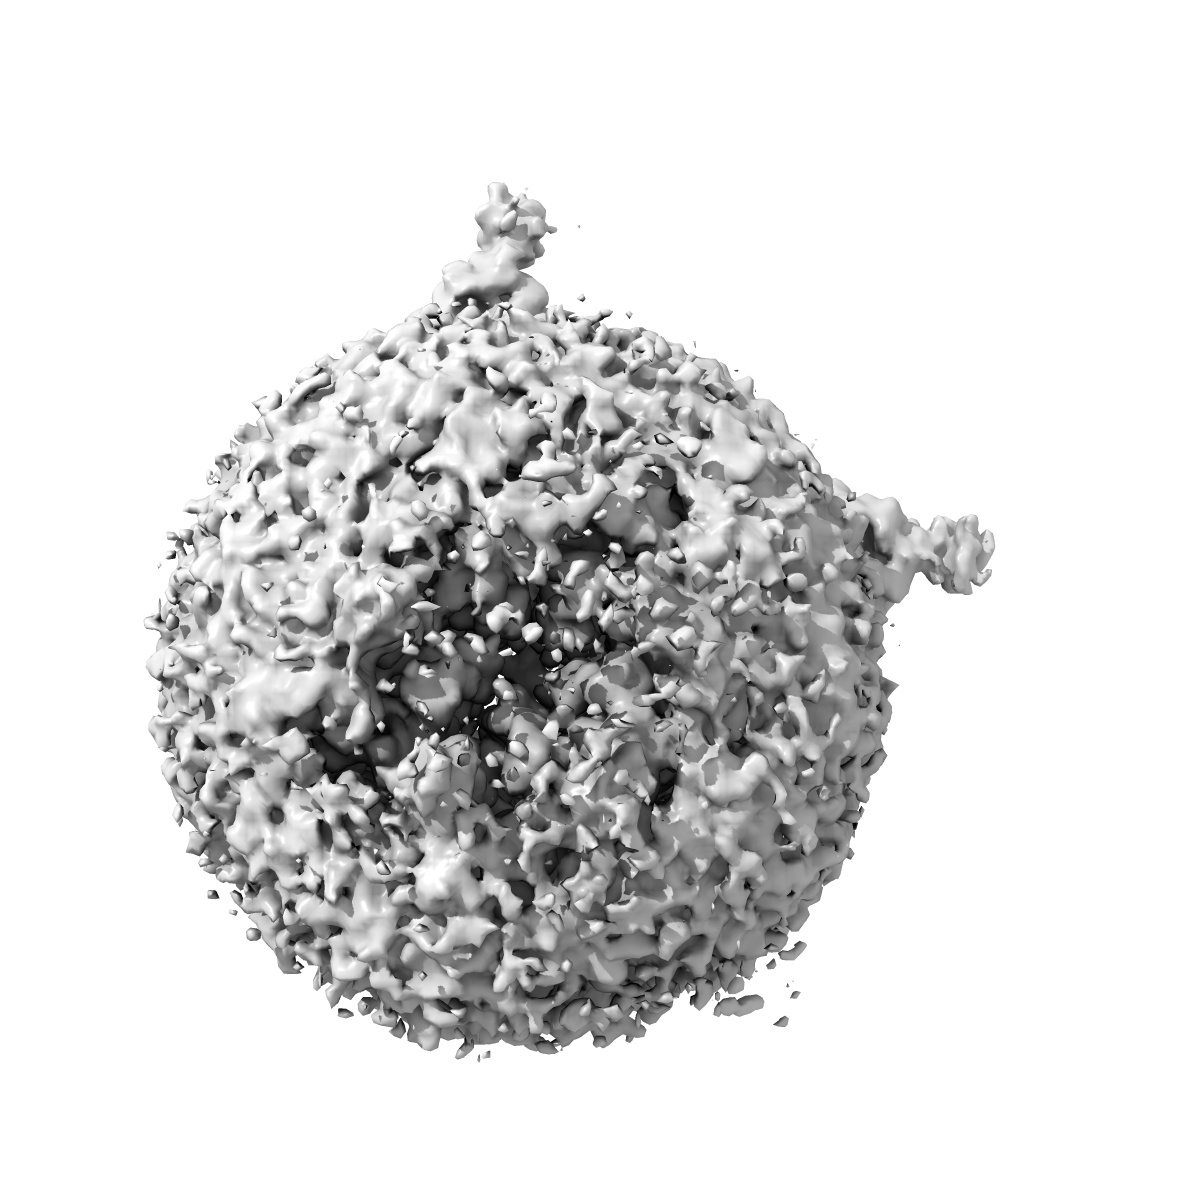

Cryo-EM structure of human full-length extrasynaptic alpha4beta3delta GABA(A)R in complex with GABA, histamine and nanobody Nb25 in a pre-open/closed state

Single-particle2.9 Å

Sample: Human full-length extrasynaptic alpha4beta3delta GABA(A)R in complex with histamine and nanobody Nb25